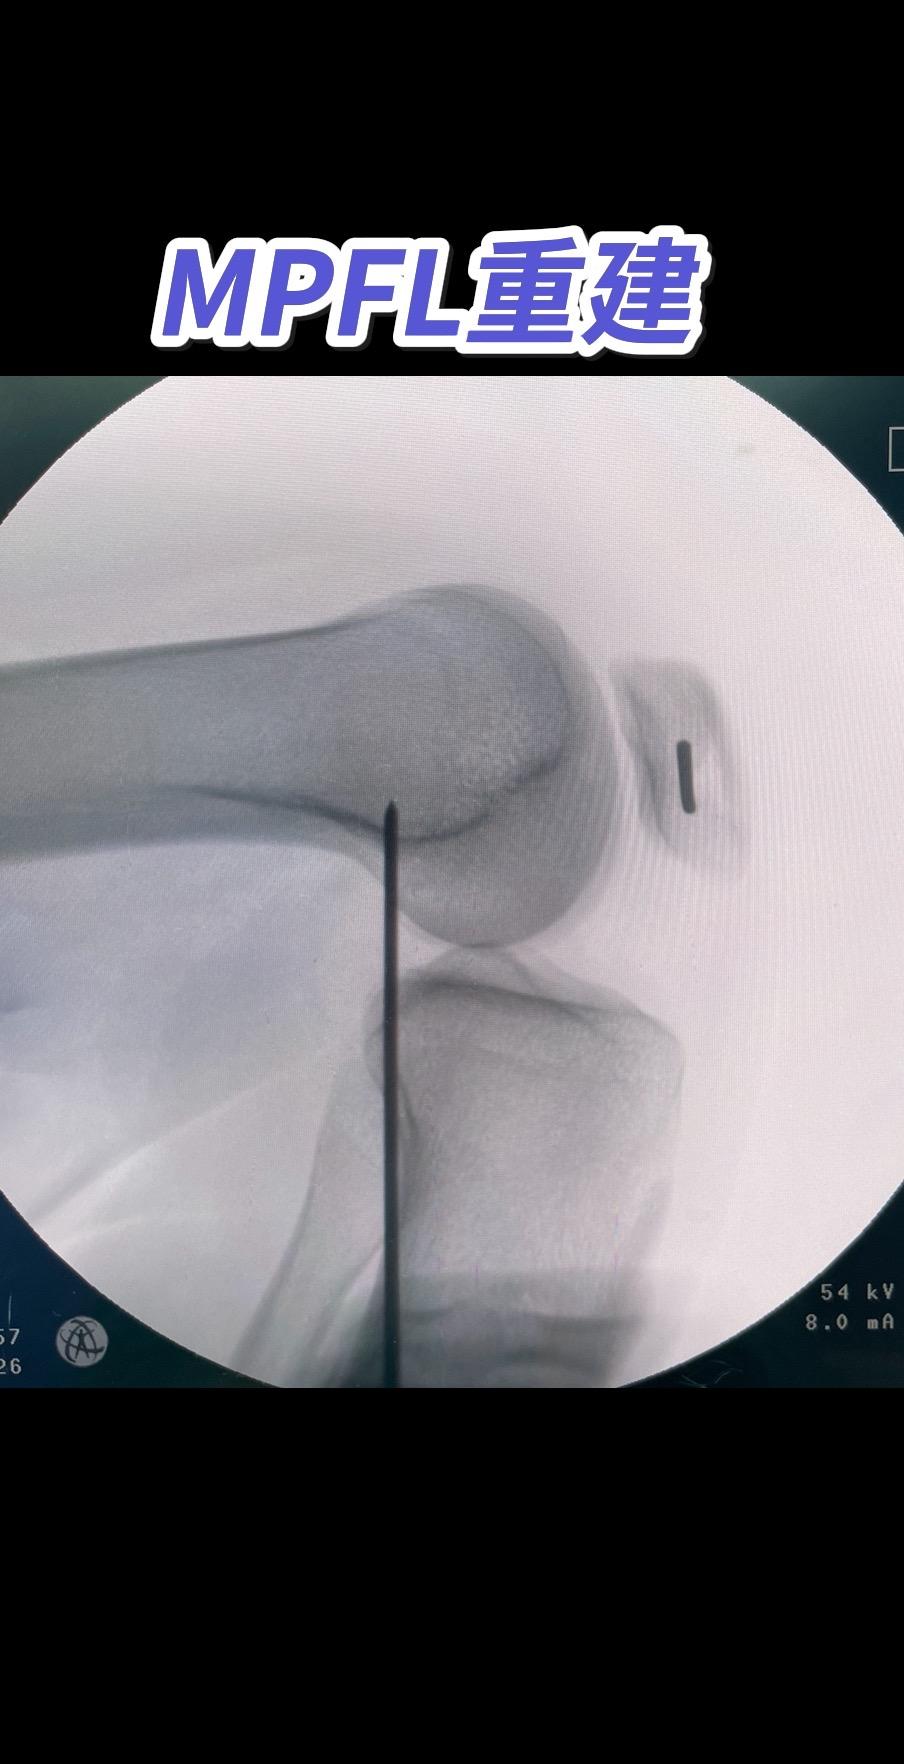

MPFL重建。

看骨科的叶培